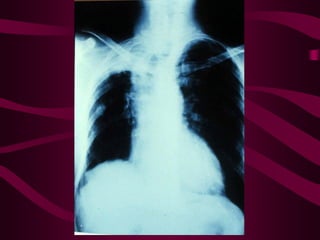

Este documento describe la tuberculosis genitourinaria. Afecta más a hombres que a mujeres. Se transmite principalmente a través de la infección pulmonar primaria y luego se disemina a través de la sangre a los riñones u otros órganos. Causa lesiones como granulomas y necrosis si no se controla, lo que puede provocar complicaciones como abscesos e insuficiencia renal. Se diagnostica mediante pruebas de orina y tratamiento con medicamentos durante varios meses.